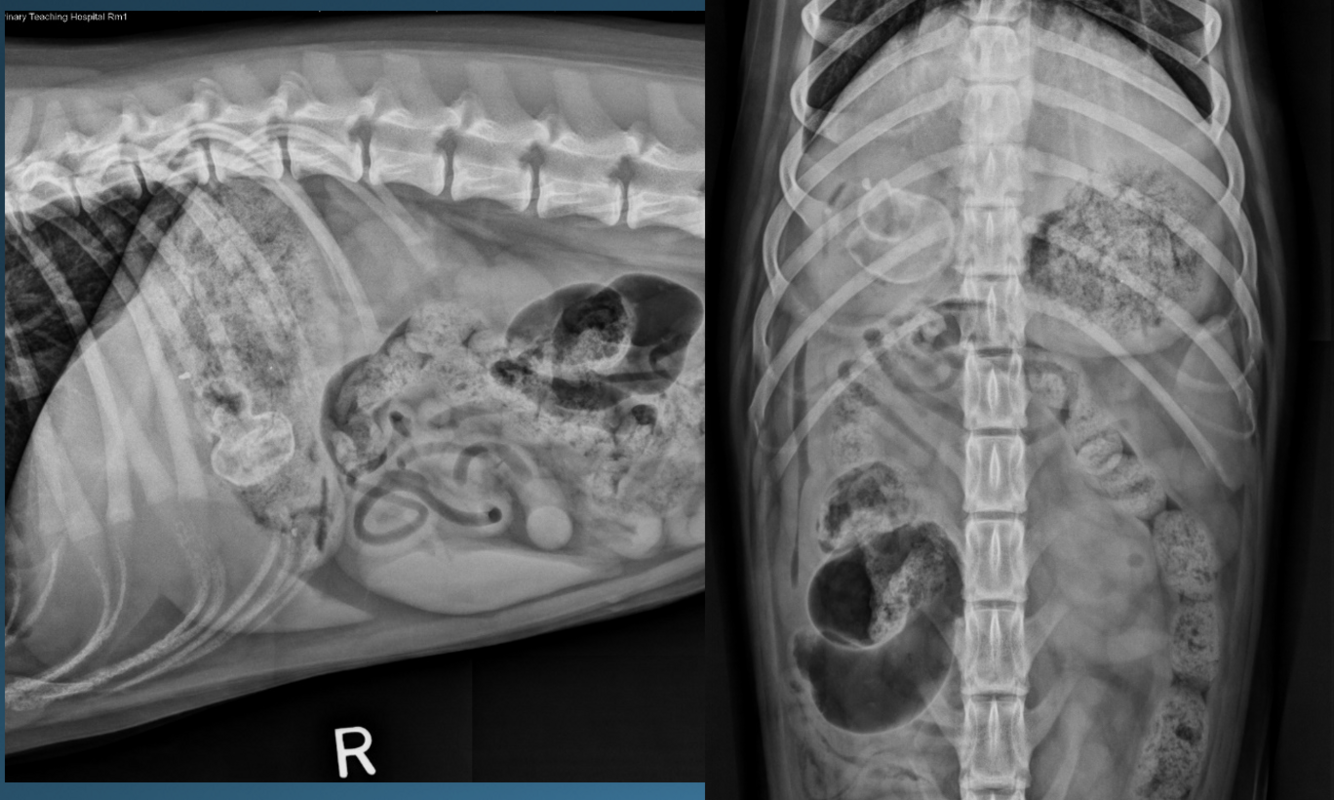

What is shown in these images?

canine acute gastric dilation

-pylorus is still in the normal place; right and more ventral